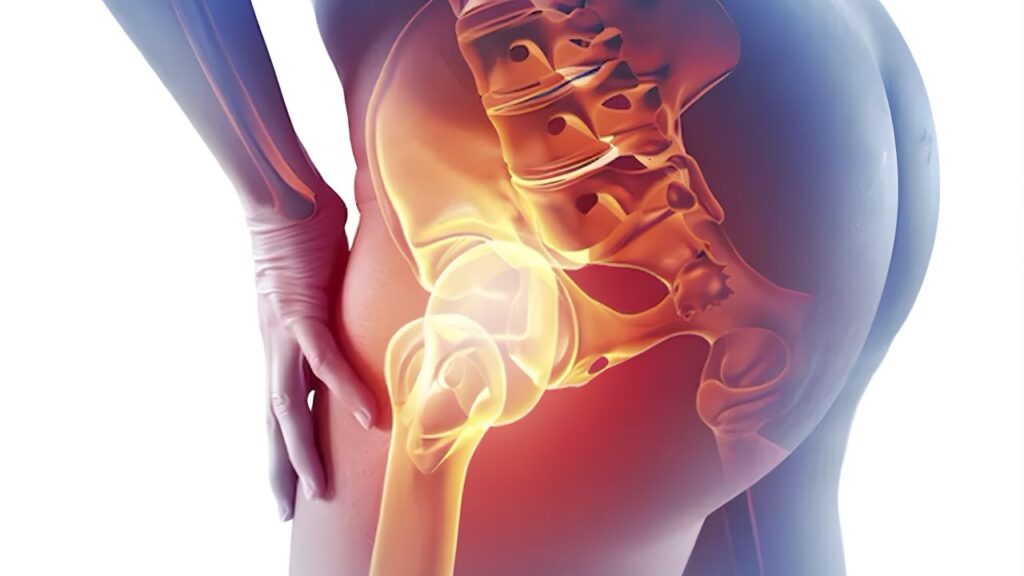

Principais causas da lesão labral As causas variam desde traumas agudos em acidentes ou quedas até o desgaste crônico por movimentos repetitivos em esportes que exigem rotação extrema do quadril, como futebol, balé e artes marciais. No entanto, a causa estrutural mais comum é o impacto femoroacetabular (IFA), onde deformidades ósseas no fêmur ou no acetábulo causam um “pinçamento” mecânico que esmaga e rompe o labrum durante o movimento normal da articulação.

Tratamentos ortopédicos e reabilitação O tratamento inicial foca na fisioterapia especializada para fortalecer a musculatura estabilizadora e corrigir desequilíbrios posturais que sobrecarregam a articulação. Procedimentos de intervenção, como infiltrações articulares, podem ser usados para controle da dor. Nos casos em que a dor persiste ou há bloqueio mecânico, a cirurgia por artroscopia é indicada para realizar o reparo (sutura) do labrum ou a reconstrução da estrutura, tratando simultaneamente as causas ósseas do impacto.